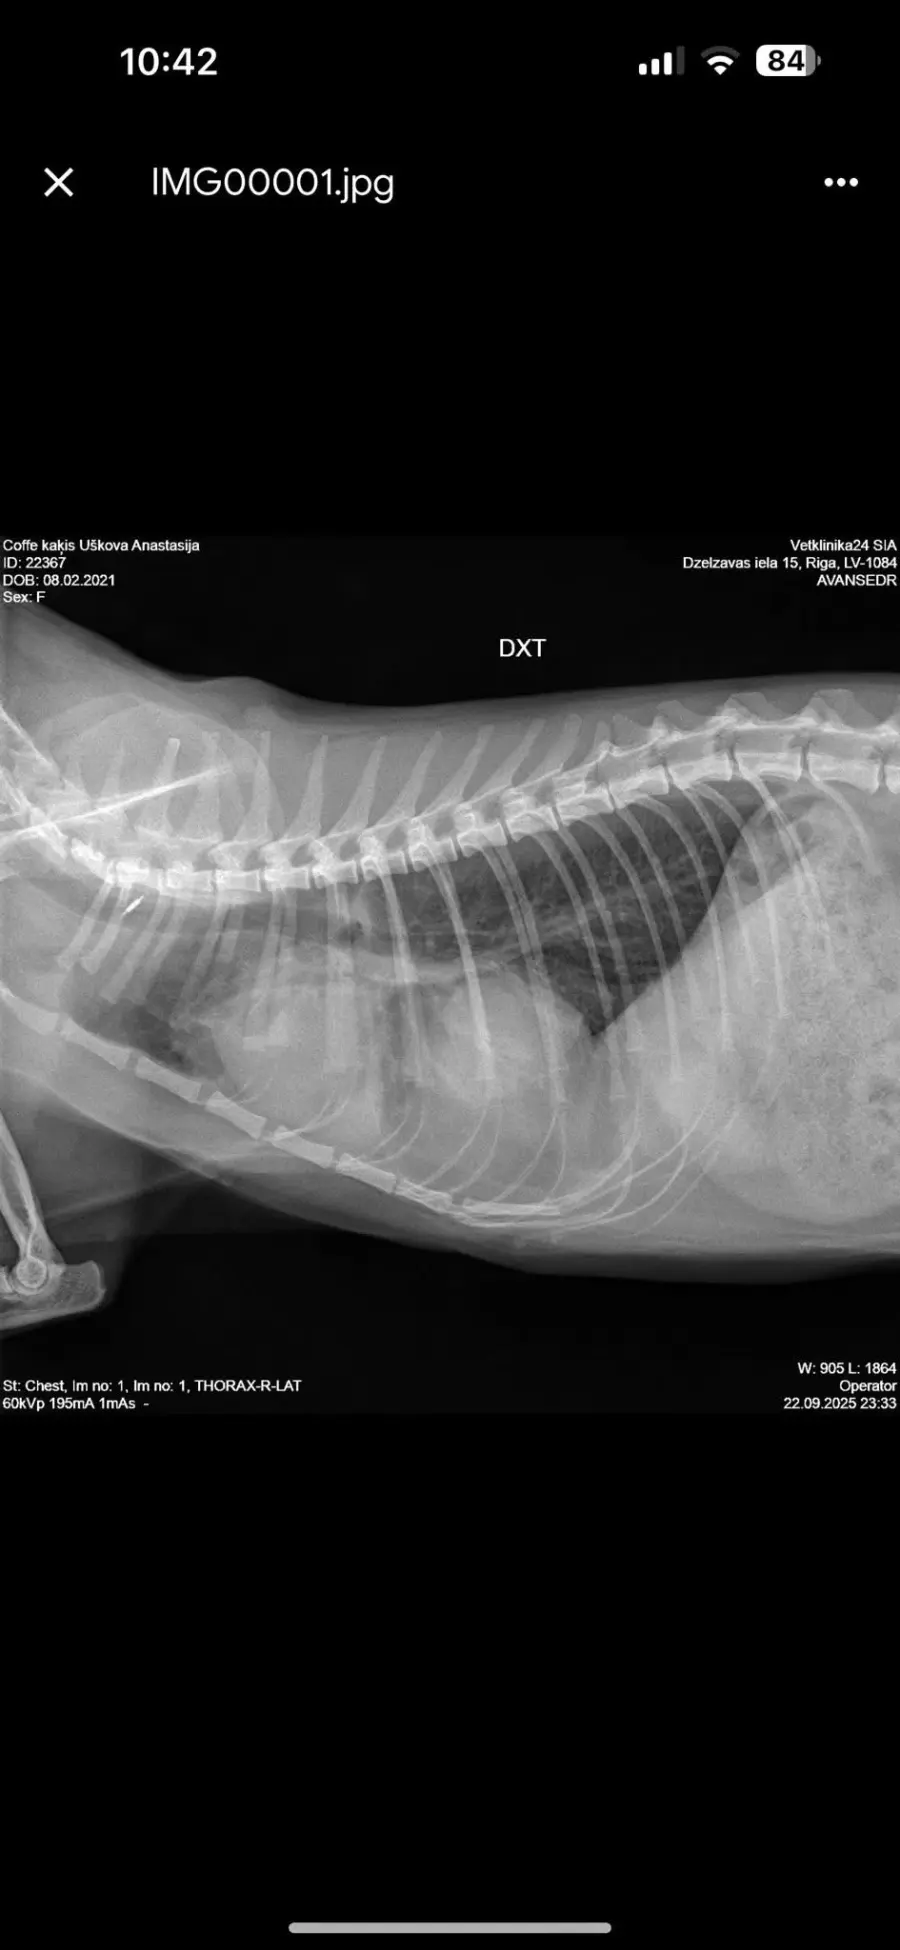

Хочу поделится своей историей покупки взрослой кошечки породы Девон рекс у заводчицы Zainaba Balabaja из питомника «Bambielf Mystery», которая в итоге оказалась больная, с врожденной деформацией диофрагмы, сросшимися органами, сжатым правым легким и еще кучей других проблем. Питомник зарегистрирован на имя её дочери Ирины Скобовы в Саласпилсе, по факту заводчица проживает и разводит котят в плявниеках. Если вкратце, весной 16го марта я приобрела у заводчицы кошечку породы Девон Рекс 4х лет, которая использовалась для разведения котят. Я и мой молодой человек созвонились с заводчицей и приехали к ней в скором времени посмотреть кошечку. В квартиру она нас не пустила, аргументируя тем что она и её муж возрастные, переболели ковидом и никого не пускают, а я наивная во все это поверила, так как это был мой первый опыт с заводчиками. Кошечку вывели на лестничную клетку в переноске, визуально она выглядела здоровой. Мы договорились об оплате наличными в размере 450 евро, о перерегистрации паспорта на меня и стерилизации через месяц в рекомендованной ей клинике, так как кошке недавно делали прививку. Договор и родословную она мне не выдала. Когда я забирала паспорт, она сказала что родословная нужна в том случае если я собираюсь водить кошку на выставки, и я решила не платить за перерегистрацию родословной на меня, так как не планировала кошку ни разводить, ни участвовать в выставках. Когда кошка начала жить у меня, спустя некоторое время у нее начали слезится глаза, заводчица уверяла что это из-за прививки. После я начала замечать что кошка часто чешется в районе подбородка и ушей, глаза все время слезились и она начала кашлять. После стерилизации кашель ухудшился, на что в клинике мне ответили что скорее всего кошка аллергик, сделали ей стероидный укол после чего симптомы прекратились на несколько недель, а потом все началось заново. На мои просьбы сделать анализы и рентген был отказ. После по совету ветов я водила кошку к вет дерматологу Евгении Кондратьевой на две консультации, были выписаны медикаменты от паразитов и курс чистки ушей, но кашель и частые чесания ушей и подбородка не прекратились. После был выписан бронхиальный ингалятор, это тоже не помогло. На мои просьбы о том, что я хотела бы сделать сразу рентген и сдать анализы был отказ, мол, надо наблюдать. В итоге в один вечер у кошки был очередной приступ кашля, который длился не минуту как обычно, а около 5-10 минут с перерывами. Я и парень повезли её в клинику Vet24, где сразу сделали рентген, взяли анализы и проверили на клещей. Какого было наше удивление когда вет принесла рентген с непонятным большим образованием давящим на органы, сказала что это не похоже на рак, но нужно делать КТ и проверить сердце. В итоге через пару дней ей сделали КТ, через месяц проверили сердце. Есть еще подозрение на проблемы с печенью, анализы на мочу показали наличие кристаллов песка. В итоге у кошки диагностировали PPDH, вкратце у кошки пока она была в эмбриональном развитии неправильно сформировалась диафрагма, образовалось отверстие и через него вышла печень и срослась с сердечной сумочкой. Органы давят на левое легкое. Правое сжатое. Сердце при этом, слава богу, пока что в порядке. Отдали мы на ветов уже больше 1000 евро, успели поменять куча кормов чтобы уменьшить симптомы аллергии и чтобы не было нагрузки на печень, переодически используем стероидный ингалятор, кошке предстоит пожизненное наблюдение у ветов, ежегодные обследования. После консультации с хирургом был сделан вывод что операцию делать смысла нет, так как с большей вероятности кошка просто умрет от потери крови. Если еще учитывать, что кошка давала потомство минимум раз в год за свои 4 года, котята давили на и так деформированные органы, а кашель заводчица просто не могла не замечать, у меня складывается подозрение что заводчица за всю жизнь кошки даже нормально ее ни разу не обследовала у вета, хотя животное ей создавало доход. Так же я нашла отзыв на sudzibas.lv за 2023 год, где мужчина приобрел двух котят у этой же заводчицы, которые оказались с клещами и хламидиозом. Жалобу я, конечно же, увидела слишком поздно. Та же схема, не пускает в квартиру посмотреть котят под предлогом ковида и уверяет что котята здоровые, а слезящиеся глазки после прививки. Сумма на ветов и обследования за пол года уже привысила 1000 евро и бог с этими деньгами на лечение, меня больше всего злит обман и абсолютное потребительское отношение к животным, которые создают тебе доход. С заводчицей после получения вет паспорта я в дальнейшем не контактировала, так как не вижу смысла выяснять отношения с человеком, который меня намеренно обманул и продал больное животное. Считаю что здесь нужно подключать соответсвующие инстанции. Скрины заключений, КТ, рентгенов прикреплю к посту. Так же сохранились скриншоты переписок с заводчицей, объявление о продаже кошки, большая часть выписок и переписок с ветами.

Прикладываю копию рентгена, результата КТ, объявление о продаже кошки, профиль заводчицы и название питомника в списке клуба Mooncat сюда в комментарии